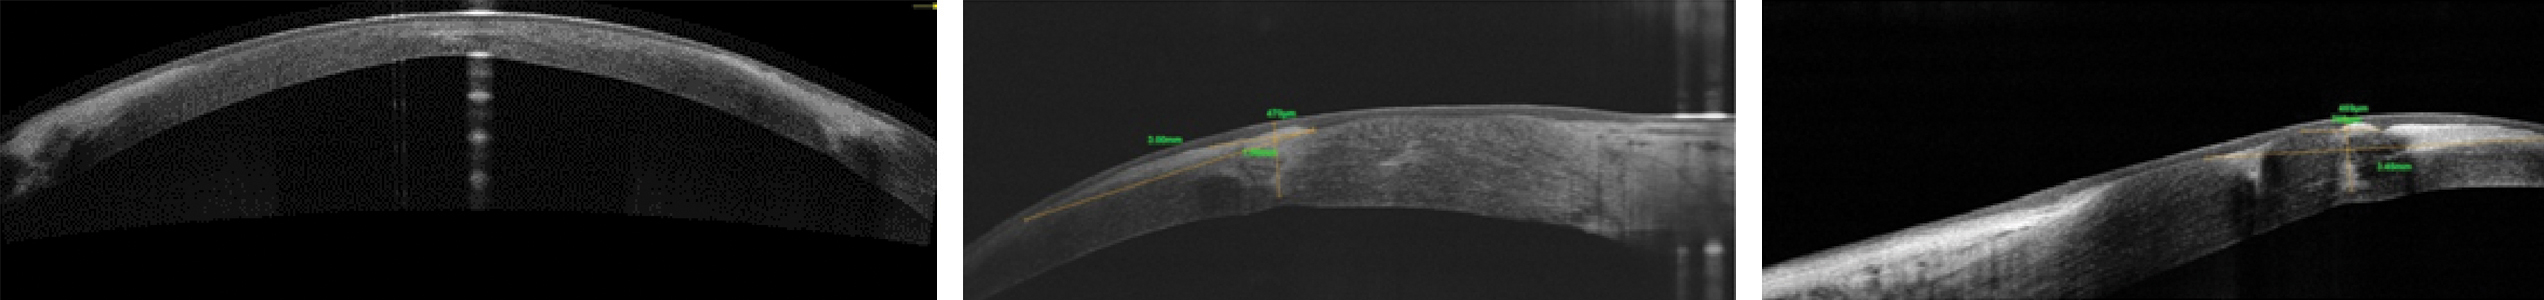

При оценке зоны рубца по снимкам оптической когерентной томографии через 12 месяцев определялись формирование клиновидного гиперрефлективного помутнения с распространением в толщу стромы роговицы на 2/3 глубины, выраженное фиброзирование послеоперационного рубца (рисунок 6).

Рисунок 6. ОКТ переднего отрезка глаза через 12 месяцев после модифицированной методики ФРАК: формирование клиновидного гиперрефлективного помутнения с распространением в толщу стромы роговицы на 2/3 глубины, выраженное фиброзирование послеоперационного рубца.

Figure 6. OCT of the anterior segment of the eye 12 months after the modified FRAK technique: the formation of a wedge-shaped hyperreflective opacity with a 2/3 depth spread into the thickness of the corneal stroma, pronounced fibrosis of the postoperative scar.

Наличие у всех пациентов, вошедших в исследование, выраженного фиброзирования в зоне выполненного в ходе ФРАК фемтолазерного реза свидетельствует об адекватной адаптации краев операционной раны. Комбинированная шовная фиксация позволила не только адекватно сопоставить края образовавшегося после фемторезекции канала, но и обеспечить максимально равномерное натяжение роговичной ткани, тем самым избежать изменений заднего профиля роговицы, а также уменьшить выраженность послеоперационного астигматизма.